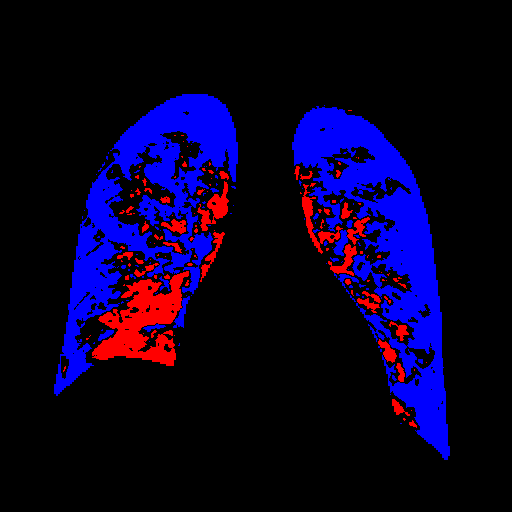

Side-by-side inspection of the generated healthy counterfactuals (as per fig. 2) suggests that, as required, only minimal perturbation is made to the original image with respect to healthy pixels -i.e. localized image sites without structural medical defects. (In the top row, the medical structural defect in the original image is due to a lung opacity, and characterized via a relatively complex interaction between the imaging modality and subject manifesting as ‘gaps’ in the corresponding portions of the lung scan). The healthy/non-healthy discrepancy maps in all of these cases are obtained via masked subtraction of the original image from the generated image (the ground truth segmentation masks correspond to the broad area of interest –i.e. the complete lung). The generated healthy tissue is thus a subset of the mask and is shown in the final column of fig. 2 for the respective cases.

In the context of a VANT-GAN[20]-based approach, this highlighted material constitutes the diagnostic counterfactual visual attribution, i.e. the selection of material relevant to the diagnosis of the unhealthy condition. Healthy counterfactual generation was performed for the complete datasets in the three unhealthy classes, i.e Lung opacity, Viral Pneumonia and COVID, examples of which are given in fig. 3 for the three classes (all of the generated healthy counterfactuals from this experiment can be found on https://huggingface.co/ammaradeel/diffusionVA). Visual inspection indicates that the generated counterfactuals are, in general, visually plausible with minimal perturbation made to the unhealthy image overall. Moreover, the healthy counterpart generation does not appear to unnecessarily affect aspects of the images unrelated to the medical condition, the model selectively making changes to the unhealthy regions in a structurally plausible manner, e.g. generating missing portions of the lung without generating extraneous lung material where it would be expected to normally exist (e.g. in the abdominal cavity).